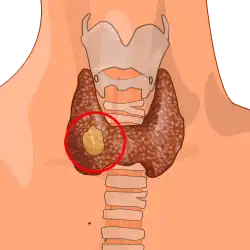

Thyroid neoplasm

| Thyroid neoplasm | |

| Thyroid anatomy | |

Thyroid neoplasm is a neoplasm or tumor of the thyroid. It can be a benign tumor such as thyroid adenoma,[1] or it can be a malignant neoplasm (thyroid cancer), such as papillary, follicular, medullary or anaplastic thyroid cancer.[2] Most patients are 25 to 65 years of age when first diagnosed; women are more affected than men.[2][3] The estimated number of new cases of thyroid cancer in the United States in 2023 is 43,720 compared to only 2,120 deaths.[4] Of all thyroid nodules discovered, only about 5 percent are cancerous, and under 3 percent of those result in fatalities.